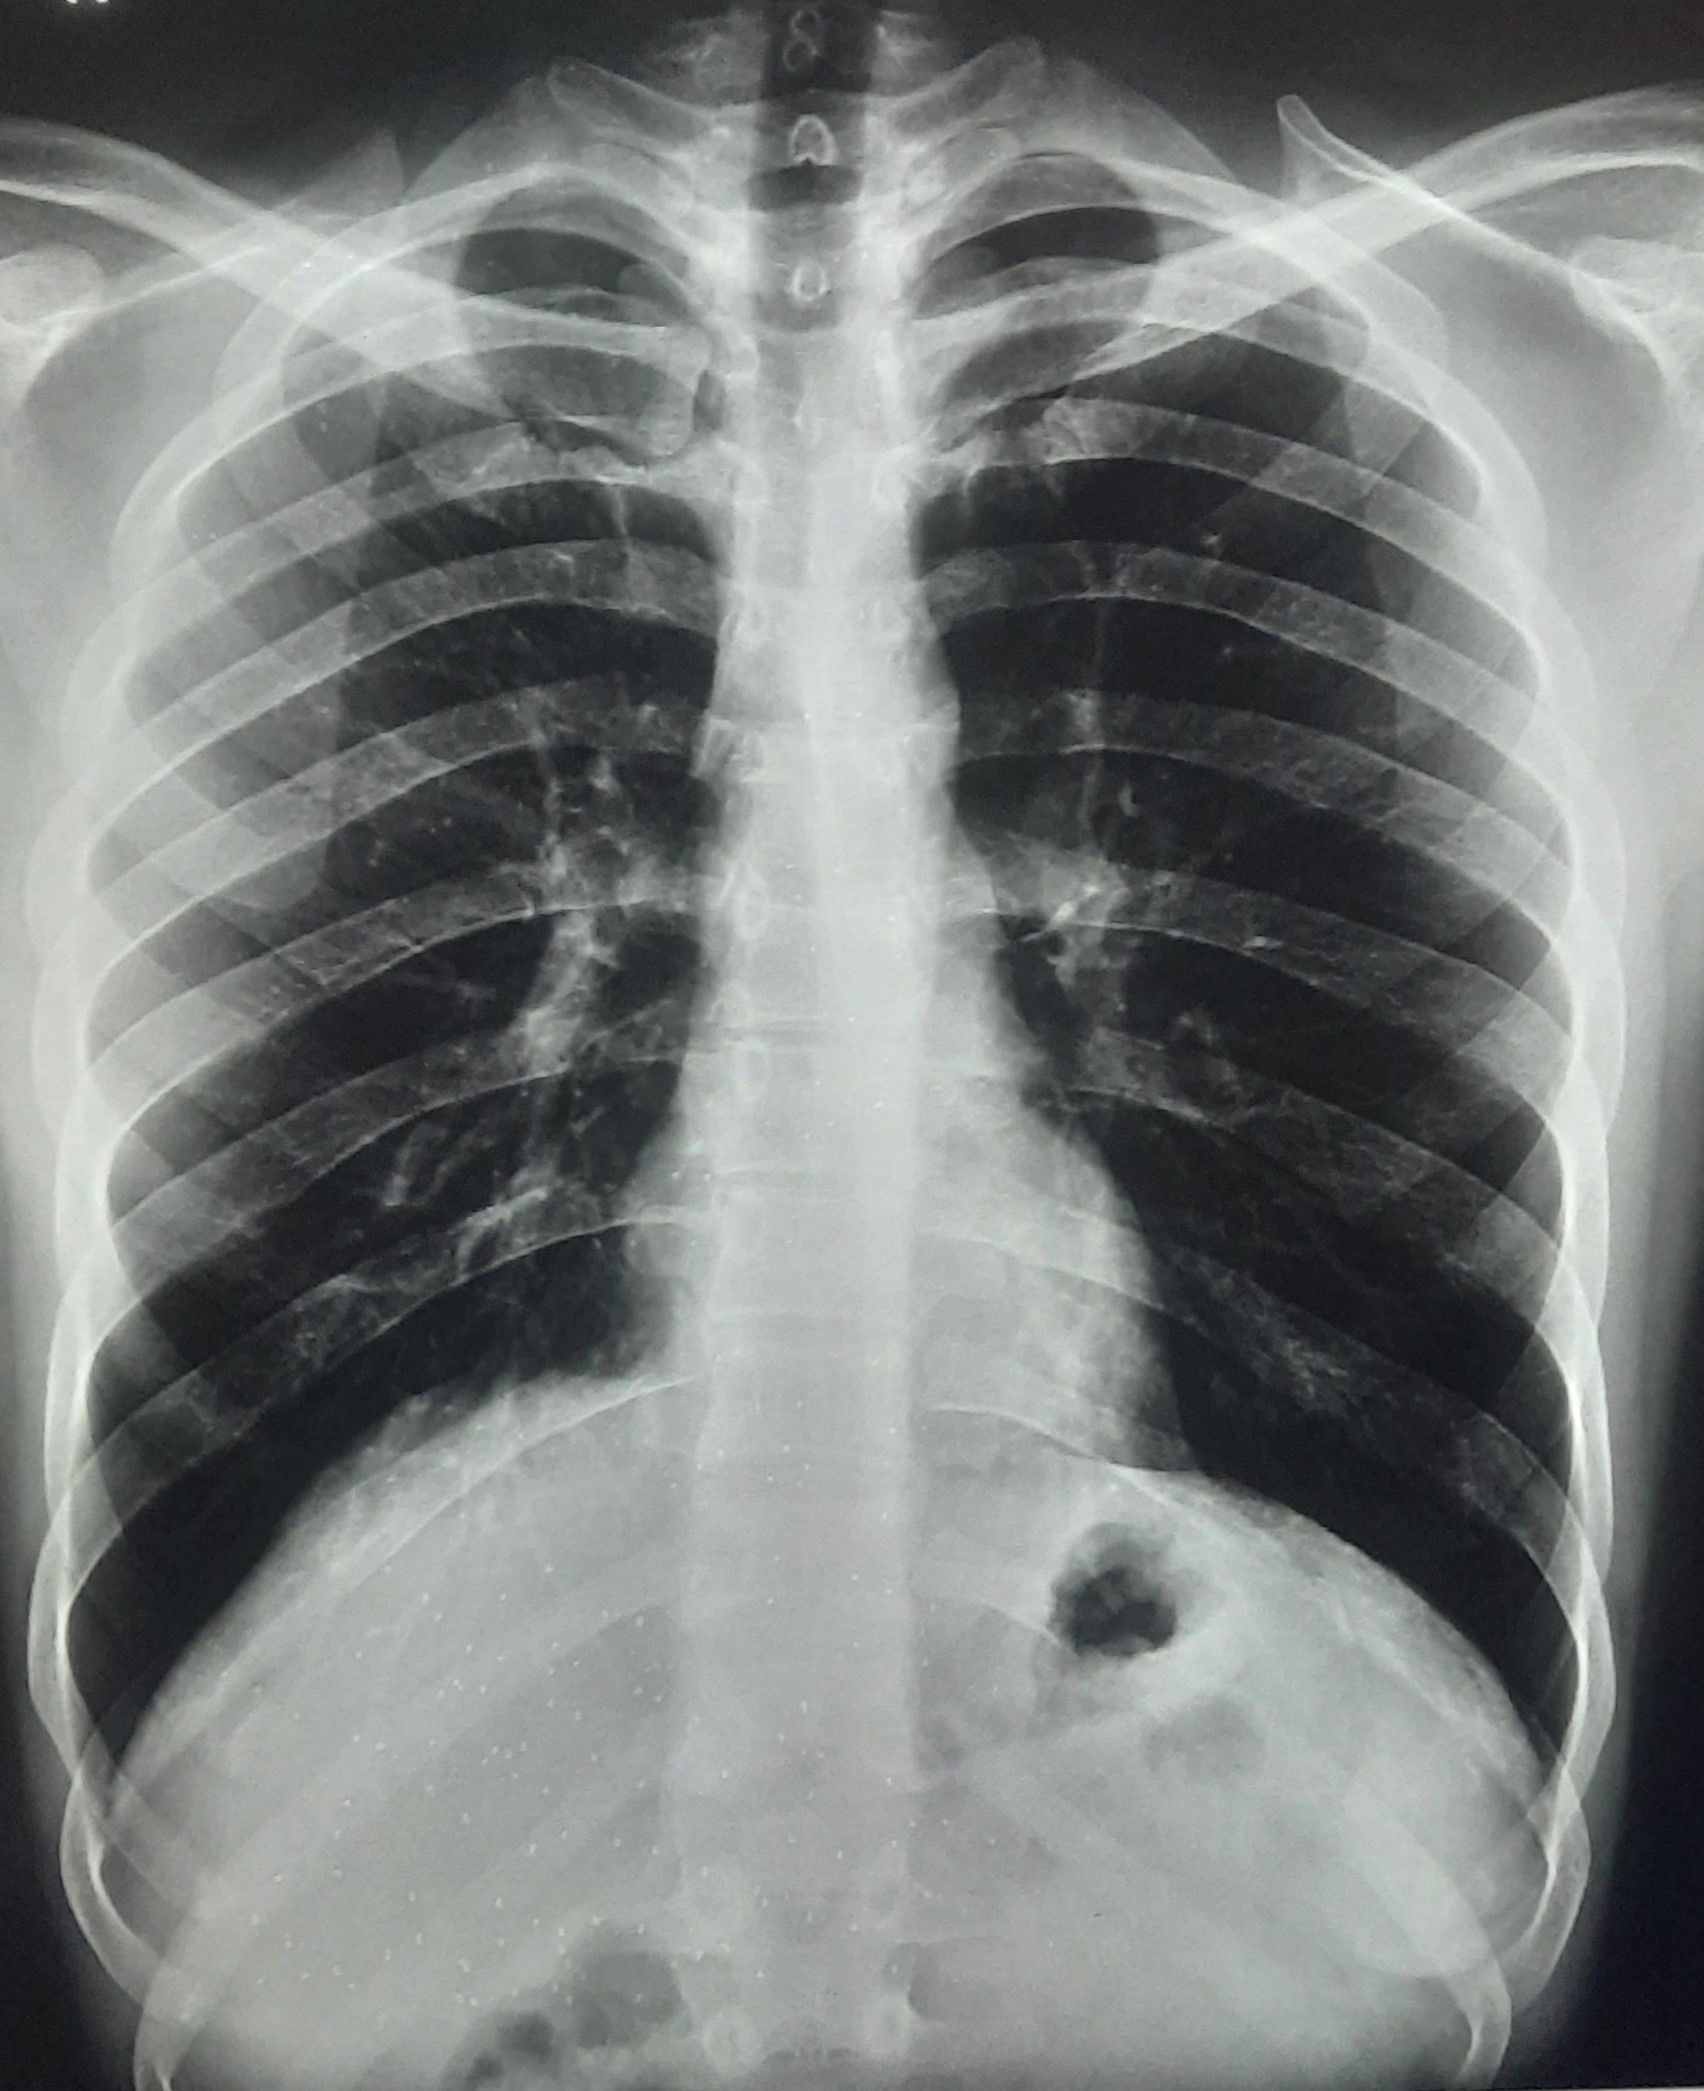

| 251 | IGGMC, Nagpur, Nagpur | P2 | 29-4221 | Ganpat Gaikawad | Consent taken on Paper | 70 Yrs. |

Provisional Diag : post TB sequele?

Final Diag : Fibrosis |

Non-TB Case (Confirmed) | Fibrosis | Abnormality visible on x-ray |